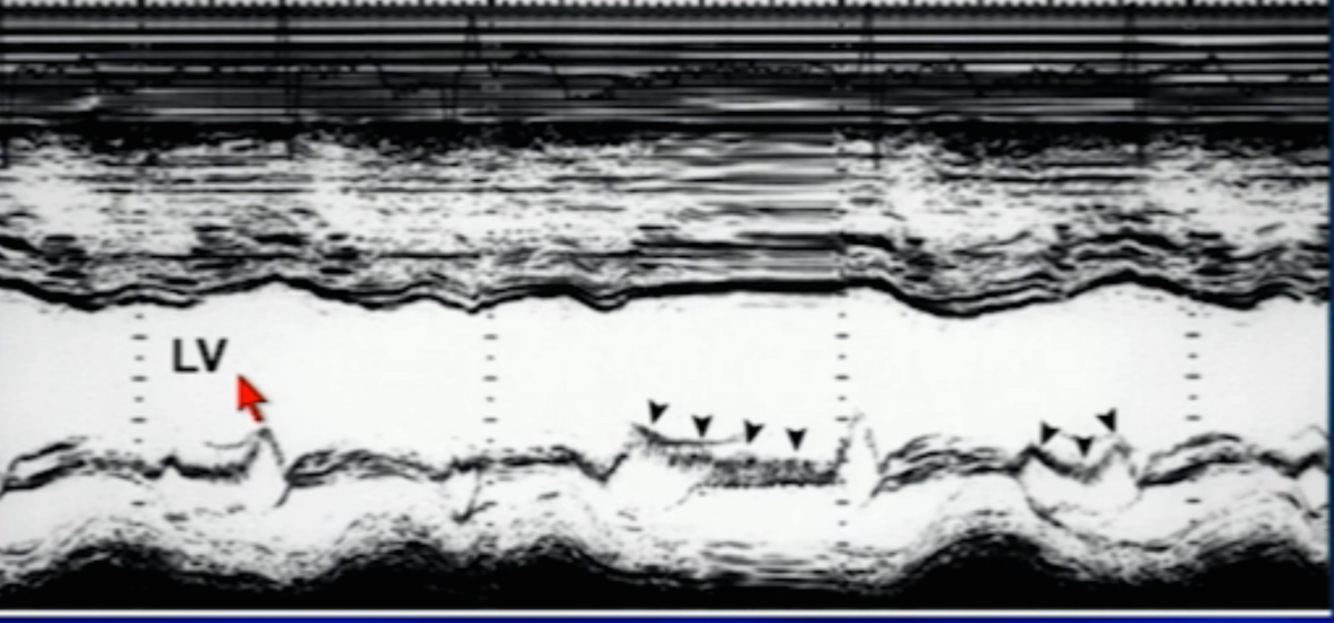

Afib

Diagnosis?

AR (LV dilated, fluttering of MV’s anterior leaflet (without loss of A wave like in afib) = austin flint)